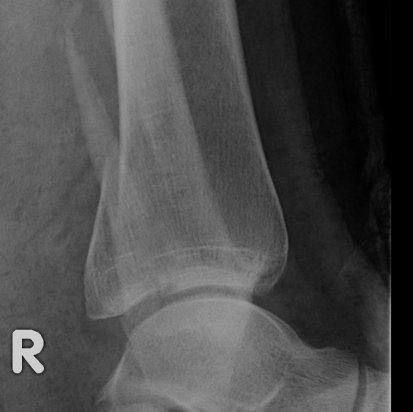

Dislocated ankle joint with large posterior malleolus

Articular incongruency

Posterior malleolus and syndesmotic injury